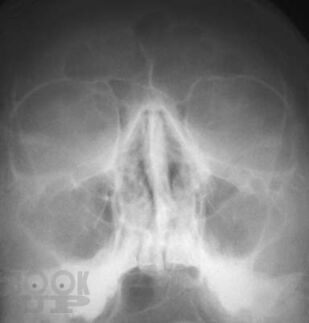

Рентгенографическая и компьютерно-томографическая диагностика острых и хронических синуситов

Монография посвящена применению классической рентгенографии и рентгеновской компьютерной томографии для диагностики острых и хронических воспалительных заболеваний околоносовых пазух. Результаты обоих исследований сопоставлены между собой по разработанной авторами методике, предложены адаптированные к практической работе подходы к обоснованному выбору указанных методов рентгенодиагностики синуситов. Книга хорошо иллюстрирована, содержит примеры описания рентгенограмм и компьютерных томограмм околоносовых пазух.